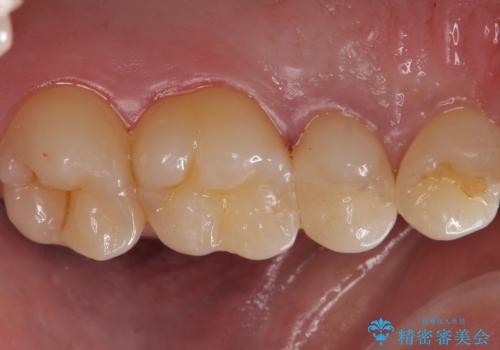

歯と歯の間の虫歯 セラミックインレーでの治療

- 検査の結果虫歯が見つかった患者様です。

レントゲン画像と視診から詰め物で対応可能と判断したためインレーでの修復をしていきます。

適合の良いインレーは段差がない上にセラミックは汚れがつきにくい材料であるため今後の虫歯発生リスクを抑えることに繋がります。